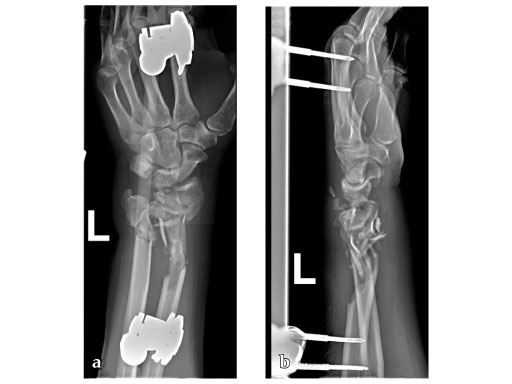

34-year-old male, with open fracture after motor vehicle accident.

Fig 1ab: Preoperative x-rays; primary stabilization with external fixator.